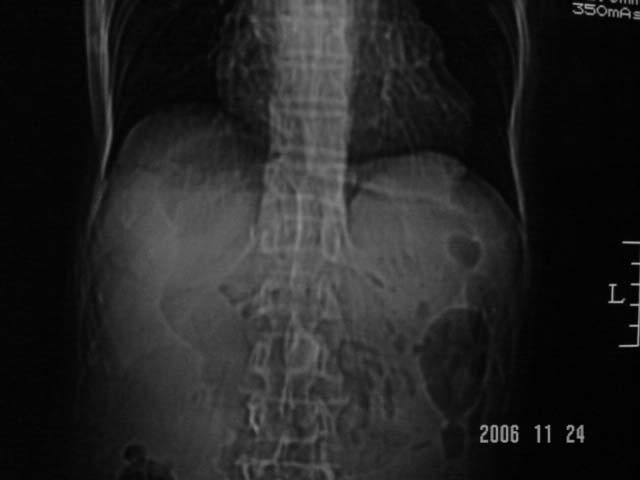

仰卧位见:肝前间隙及肝脾间隙内可见新月形气体密度影,边缘清楚,侧卧位见气体随体位改变而移动,ct值约-929hu。膈下、肝下间隙及部分肠间隙可见液性密度影。考虑:1、上腹部空腔脏器穿孔,以胃穿孔可能性大。2、少量腹水。

仰卧位见:肝前间隙及肝脾间隙内可见新月形气体密度影,边缘清楚,侧卧位见气体随体位改变而移动,ct值约-929hu。膈下、肝下间隙及部分肠间隙可见液性密度影。考虑:1、上腹部空腔脏器穿孔,结合临床,首先考虑胃穿孔可能性大。2、少量腹水

补充--肝门及肝肾间隙以见积气显示。

支持消化道空腔脏器穿孔(腹腔内大量游离气体影,小网膜囊内亦见气体影),少量腹水。